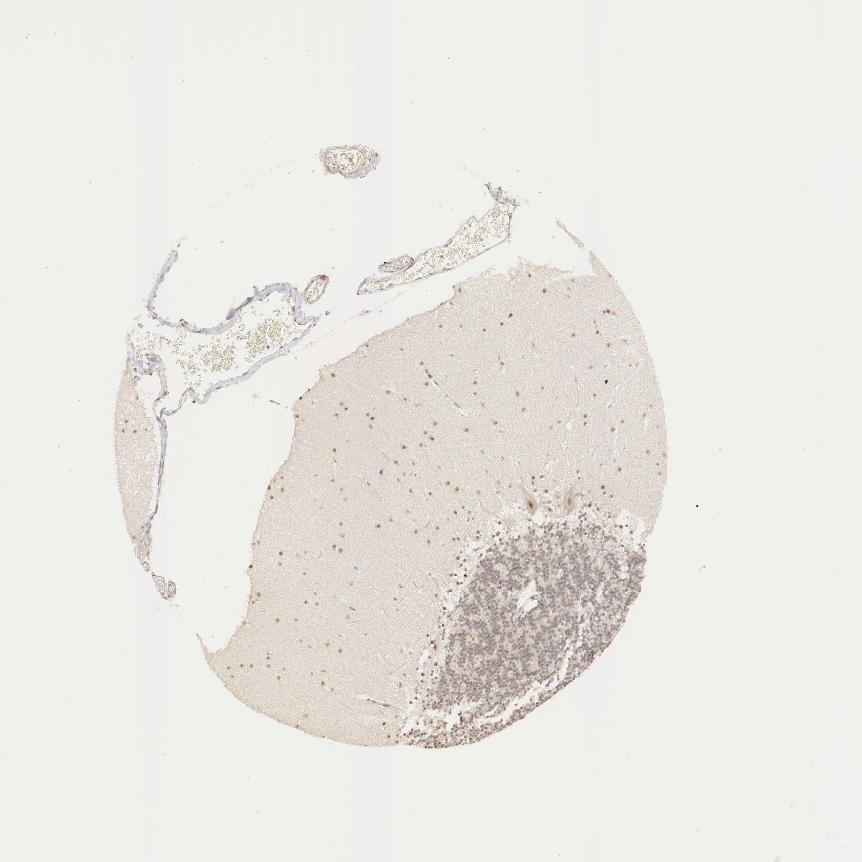

CEREBELLUM - Antibody stainingi

Antibody staining in the annotated cell types in the current human tissue is reported as not detected, low, medium, or high, based on conventional immunohistochemistry profiling in selected tissues. This score is based on the combination of the staining intensity and fraction of stained cells.

Each image is clickable and will lead to virtual microscopy that enables deeper exploration of all samples and also displays staining intensity scores, fraction scores and subcellular localization as well as patient and tissue information for each sample.

Antibody HPA000566

Purkinje cells Medium

Cells in granular layer Medium

Cells in molecular layer Low